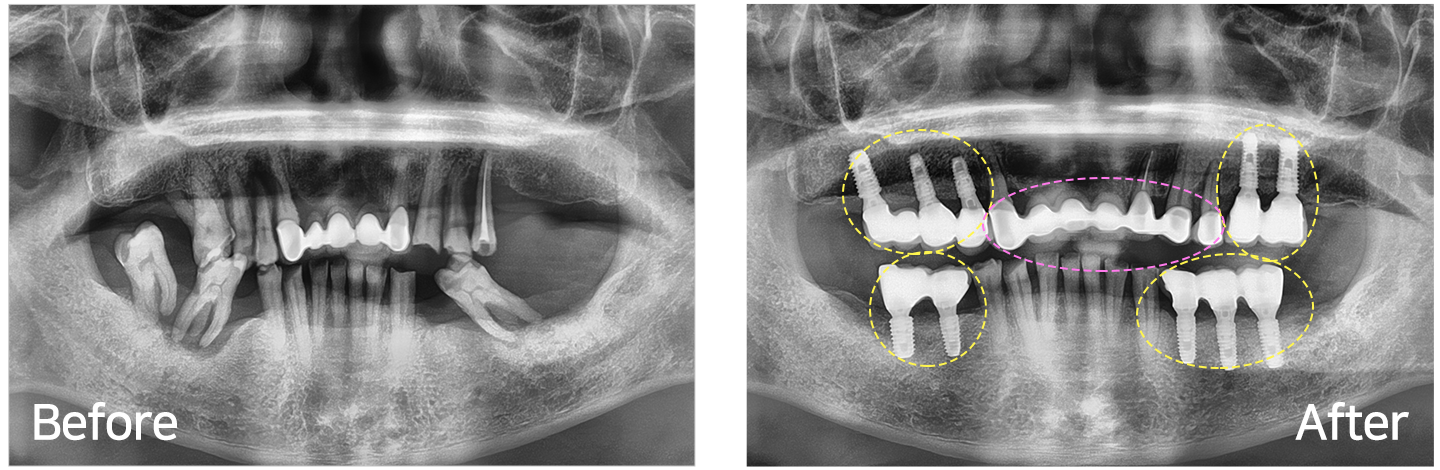

임플란트 시술 사례

IMPLANT TREATMENT CASES

※ 전신질환 및 관리 능력에 따라 임플란트 주위염 등의 부작용이 있을 수 있습니다.